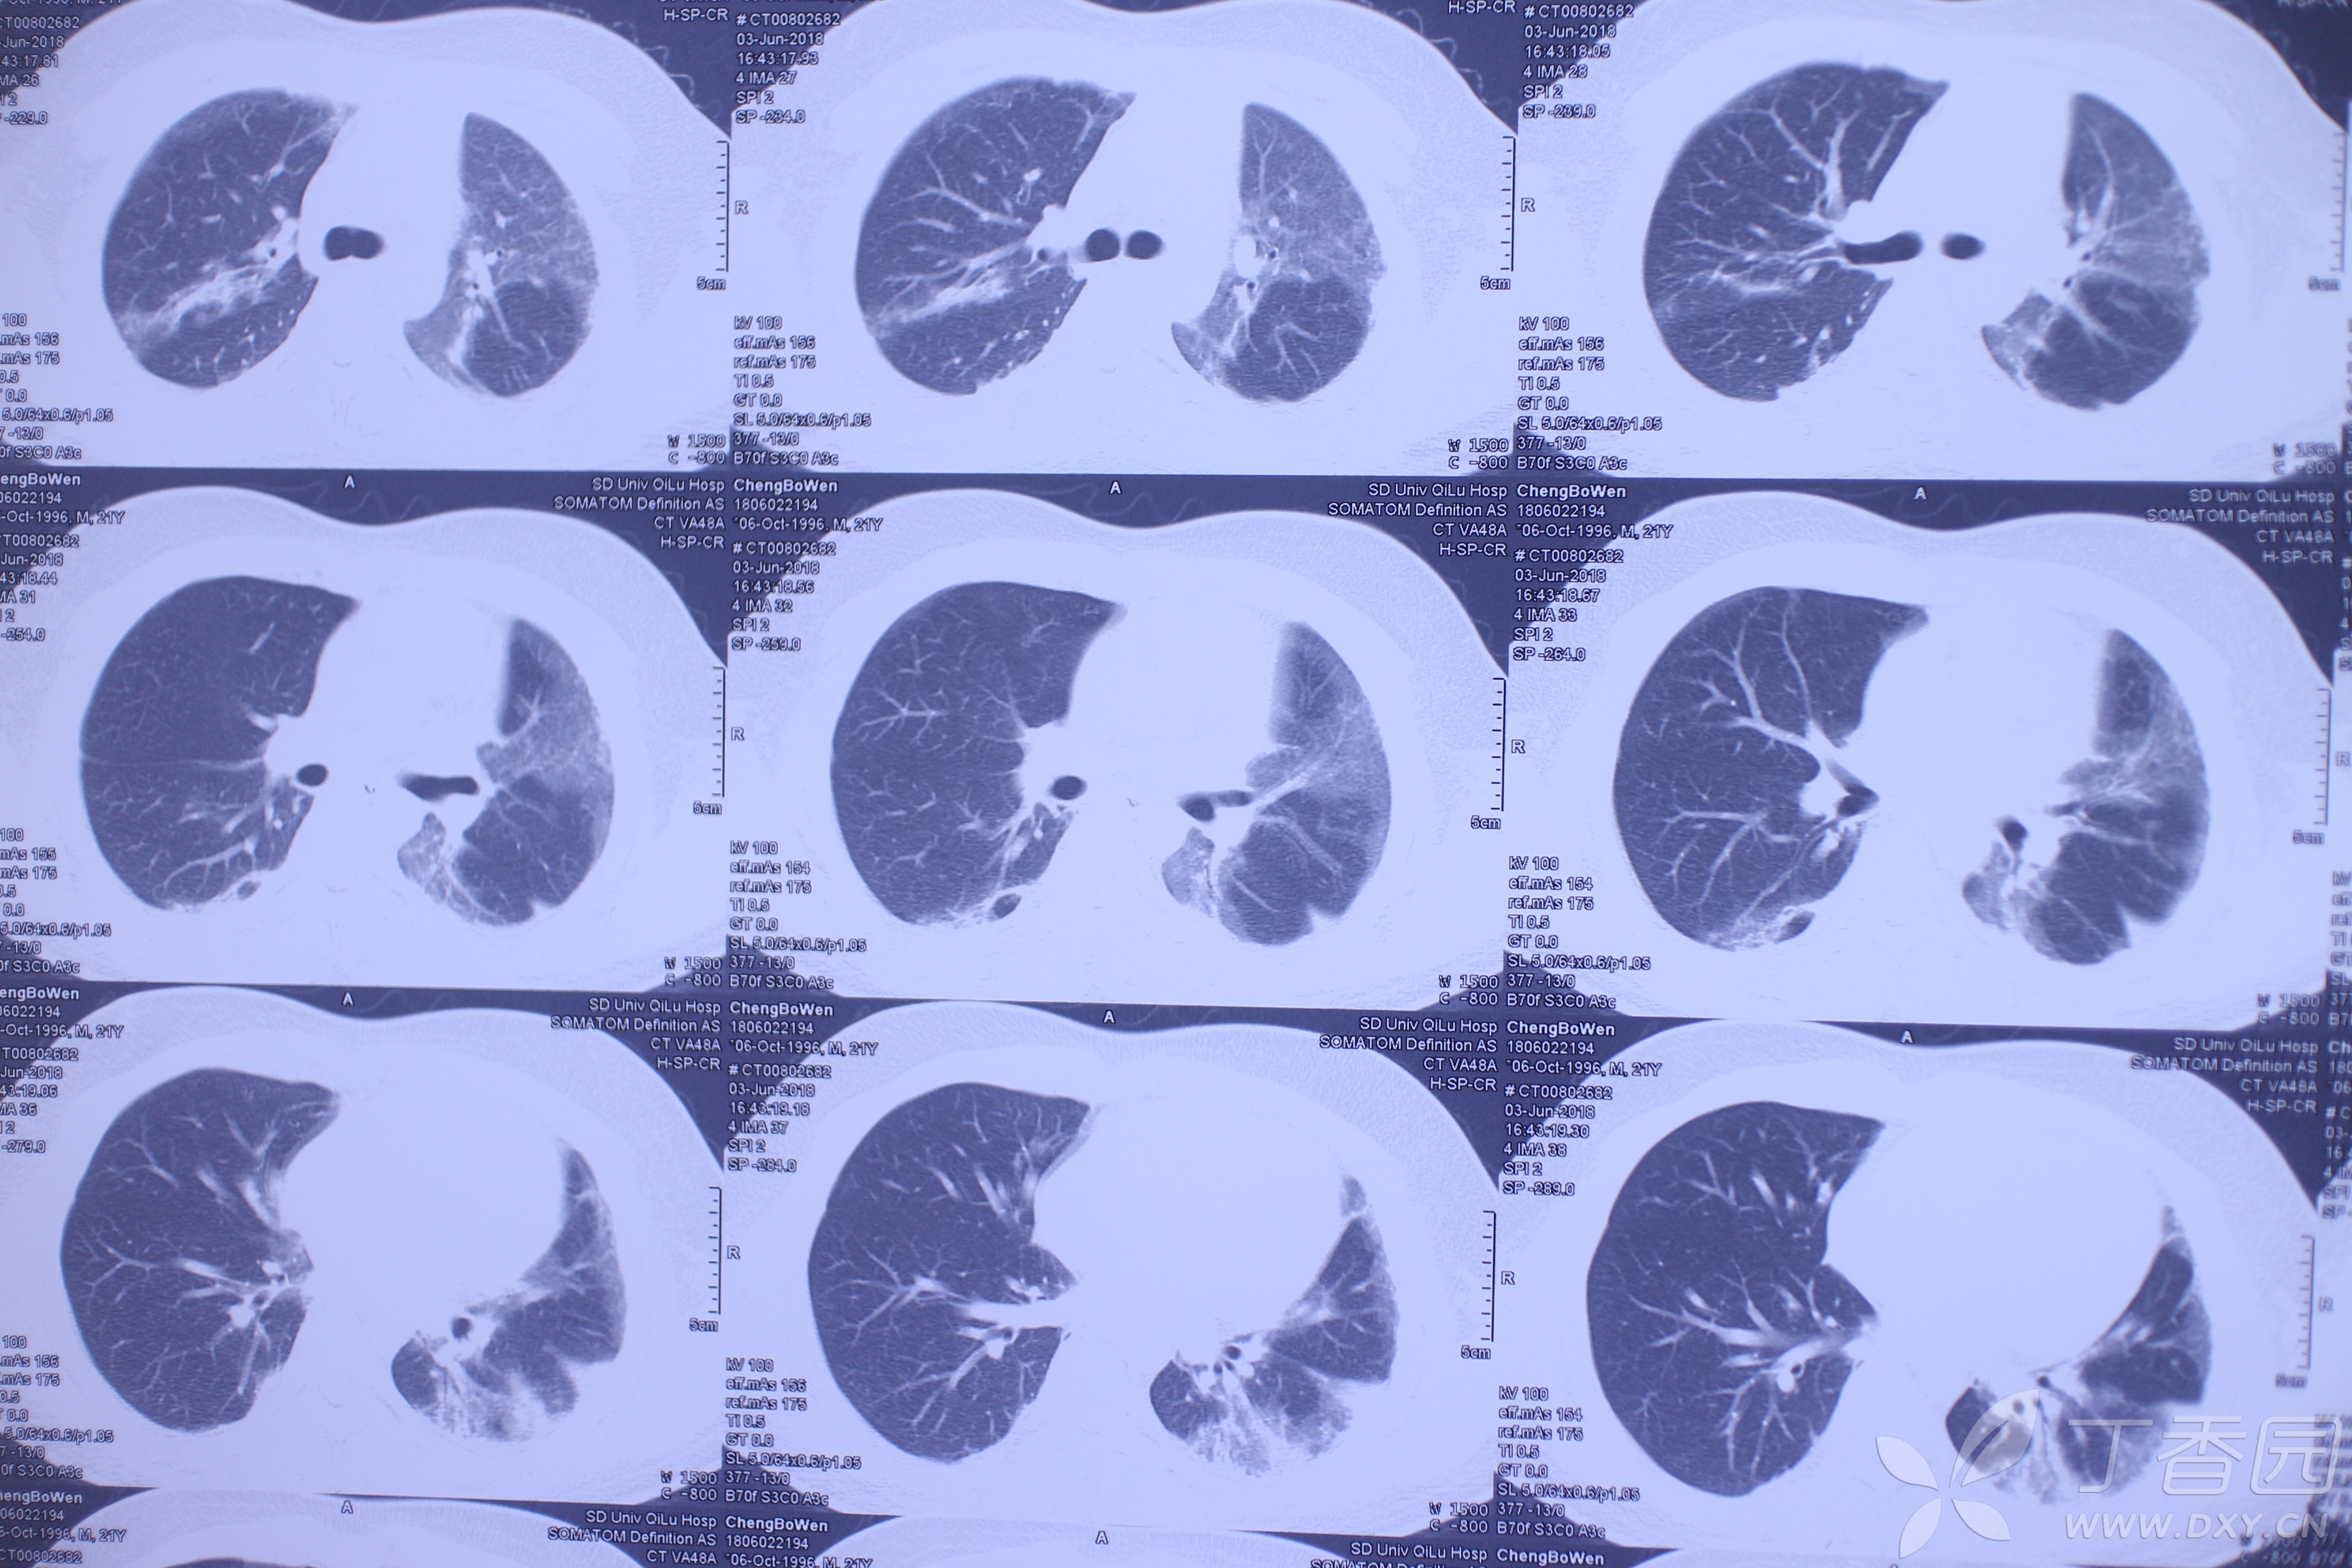

百草枯中毒病人肺片 摄影:vict

图片尺寸550x367